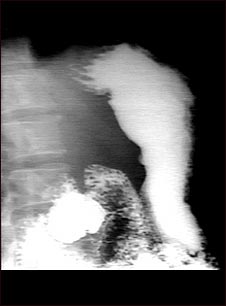

Radiografía de úlcera estomacal

Este es un ejemplo de un procedimiento llamado serie GI superior. La persona ingiere una sustancia llamada bario, que permite que se iluminen los órganos bajo estudio en la radiografía. En este caso, el paciente presenta una ulceración en el estómago que se puede observar en la parte derecha de la pantalla. Este método se utiliza para diagnosticar úlceras estomacales así como otras anomalías a lo largo del tracto gastrointestinal superior.